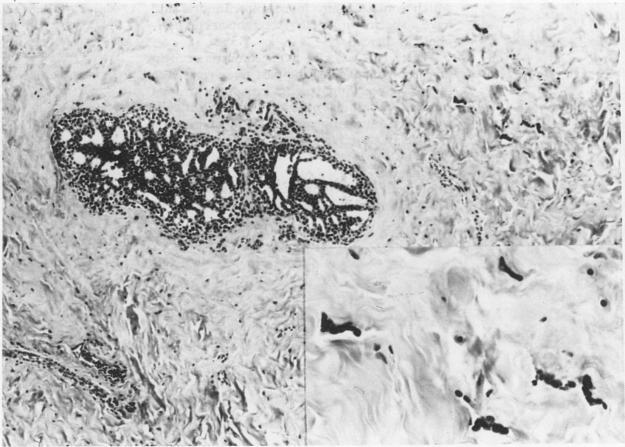

Bizzare multinucleated stromal giant cells were observed in a case of adolescent gynaecomastia. Similar cells have been described in the female breast in both benign and malignant conditions where they are thought to originate either from reactive stromal cells or from the mononuclear phagocyte system, respectively. Immunohistochemistry and electron microscopy in this case support the idea that they originate from stromal fibroblasts. Their occurrence in gynaecomastia is further evidence that these changes in stromal cells may be due to hormonal influences.

在一例青春期男性乳腺增生症中观察到奇异的多核间质巨细胞。在女性乳腺的良性和恶性病变中均有类似细胞的描述,在这些病变中,它们分别被认为起源于反应性间质细胞或单核吞噬细胞系统。该病例的免疫组织化学和电子显微镜检查支持它们起源于间质成纤维细胞的观点。它们在男性乳腺增生症中的出现进一步证明,间质细胞的这些变化可能是由激素影响所致。